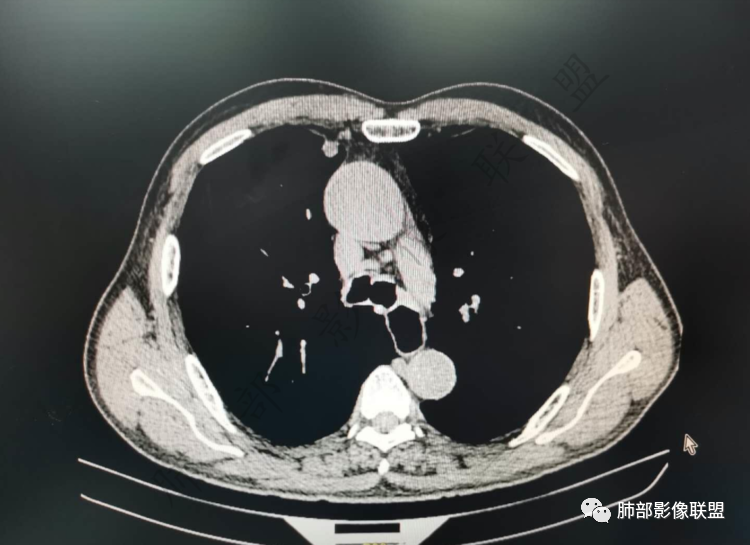

右肺上类圆形叶结节,周边见细软毛刺,增强后呈环形明显强化,内部坏死,邻近胸膜光滑,结合病史2个月明显增大,考虑炎性可能性大。

老年男性,炎性指标略高,肺气肿背景。右肺上叶胸膜下结节,部分边缘平直,部分稍膨隆,供血血管增粗,增强扫描病灶中心密度减低,呈环形强化,邻近脂肪间隙清晰。考虑炎性肉芽肿或慢性炎症,鉴别鳞癌。

老年男性,白细胞计数及CRP稍高,右肺上叶结节,两个月来有增大,部分边缘可见边界模糊的GGO,局部边缘平直、凹陷,临近胸膜增厚,内见坏死,坏死区边界未见明显壁结节,壁较厚而且均匀强化,支气管似乎有扩张然后截断,近端血管增粗明显。考虑炎性病变,脓肿?有结核病人密切接触史,注意是否为结核。有点难以理解的是为什么右侧内乳动脉增粗明显。

老年男性,无症状,炎性指标增高。肺气肿背景,右肺上叶前段结节,边缘部分平直部分澎隆,血管集束,支气管至病变边缘似截断,近端扩张。增强环形强化,中心坏死。两月内病灶增长太快,考虑炎性肉芽肿,慢性脓肿?结核?癌待排。

不要低估低分化鳞癌的倍增时间,近胸膜、生长快、坏死早。

马春平(张家港市一院胸外科): @於雄 九江市一医院影像   上周开的一例鳞癌,82岁40天从直经2cm到4cm,体积增8倍